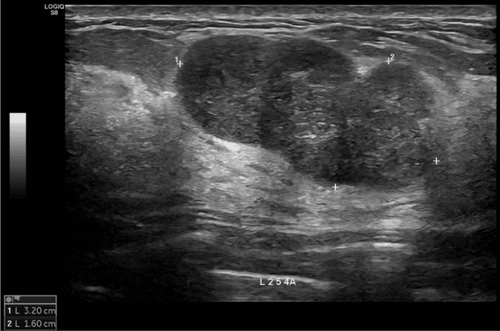

At Vinmec Times City International General Hospital, the patient was examined and found to have severe internal tibial torsion, along with other abnormalities. The deformity had an internal angle of 51.4 degrees in relation to the joint surface, a leg length discrepancy of 4 cm, pelvic tilt, scoliosis, thigh muscle atrophy, and ankle joint involvement, including deformation and degeneration of the ankle joint.

Testing for axis correction using 3D modeling software with common osteotomy techniques, such as closing and opening angles, it found that these methods were not feasible due to the large gap, which would require a large amount of bone graft or further shorten the patient's leg. It would also alter the patellar tendon length and the posterior tibial slope, affecting future knee joint function.

As a result, the doctors decided to use an inverted V-shaped osteotomy technique, where the outer tibial bone is cut and reversed to be grafted into the inner side.

After calculating the surgical plan on the computer, the patient's bone model was 3D printed for experimental surgery. After the success of the experiment, a personalized 3D-printed surgical guide was used in the surgery, allowing the surgeon to make precise bone cuts as planned, resulting in a smooth, complication-free surgery.